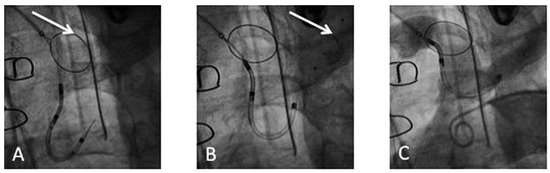

The Claret CE Pro™ device (Claret Medical Inc., Santa Rosa, CA, USA) is introduced via right radial or brachial access. It contains one filter basket to be deployed in the brachiocephalic trunk, and allows introduction of a standard filter wire to the left carotid artery [17]. The system consists of a 6 French sheath, a delivery system and the brachiocephalic filter (Figure 4). The first generation device was modified in order to allow introduction over a 0.014’’ guidewire and by modifying the bend of the distal steerable tip for antegrade probing of the left carotid artery. After deployment of the proximal filter in the brachiocephalic trunk, the distal tip of the delivery system is advanced to the aortic arch and positioned in a way to allow placement of the distal filter in the left carotid artery (Figure 5 and Figure 6).

Figure 5. Deployment of the Claret CE Pro™: (A) Deployment of the first filter in the brachiocephalic trunk (arrow). (B) Deployment of the second filter in the left common carotid (arrow). (C) Confirmation of correct device position by contrast injection in the aortic arch.